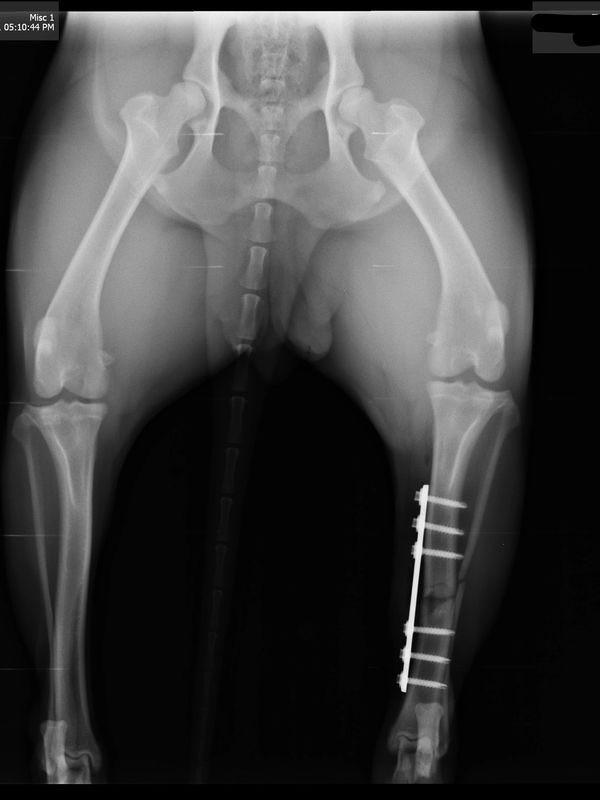

Using internal fixation, Dr. Martin repaired the fracture using a titanium plate and screws.